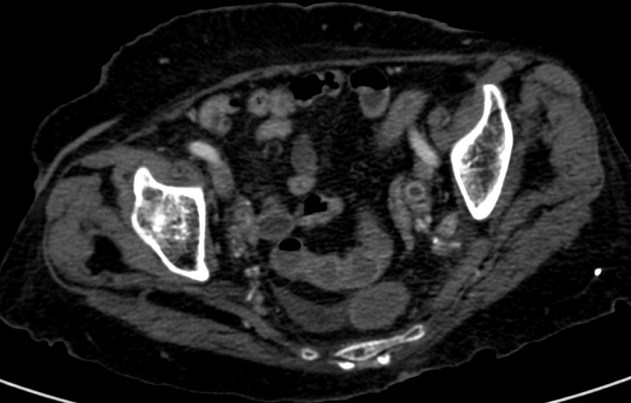

Se procede a realizar TC abdomino-pélvico con contraste en fase nefrográfica y excretora:

Conclusión: se nos presentó un caso de un paciente con una sospecha de infección renal complicada ya que tras cuatro días de tratamiento antibiótico no hubo mejoría. Ante los hallazgos observados en TC, podemos establecer el diagnóstico de pieloureteritis renal izquierda con signos de hidroureteronefrosis leve hasta vejiga.

- Protocolo: TC abominopélvico sin y con contraste en fase nefrográfica (70 seg) +/- fase tardía ( a los 7 – 10 min) solo si se sospecha obstrucción.

- TC con contraste: Las áreas afectadas del parénquima aparecen como zonas con baja atenuación debido al edema. Las áreas hiperdensas son menos frecuentes y corresponden a focos de hemorragia. Estos hallazgos son mejor valorables a través de la aplicación de contraste, ya que un TC en vacío pueden pasar desaprecibidas.